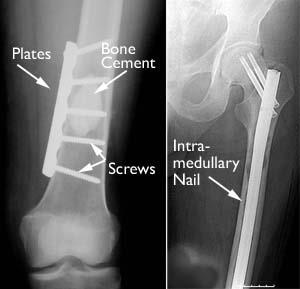

A broken or weakened bone must be carefully fixed in position and supported until it is strong enough to bear weight. During surgery, the tumor may be removed and the bone is stabilized with fixation devices, such as wires, plates, rods, pins, nails, and screws. Often, bone cement is placed into the defect created by the tumor to give added strength.

Internal fixation

(Left) This X-ray shows a large defect filled with bone cement on a thighbone. A plate and screws have been applied to support the bone. (Right)  In this X-ray, the thighbone is stabilized with an intramedullary nail and special screws.